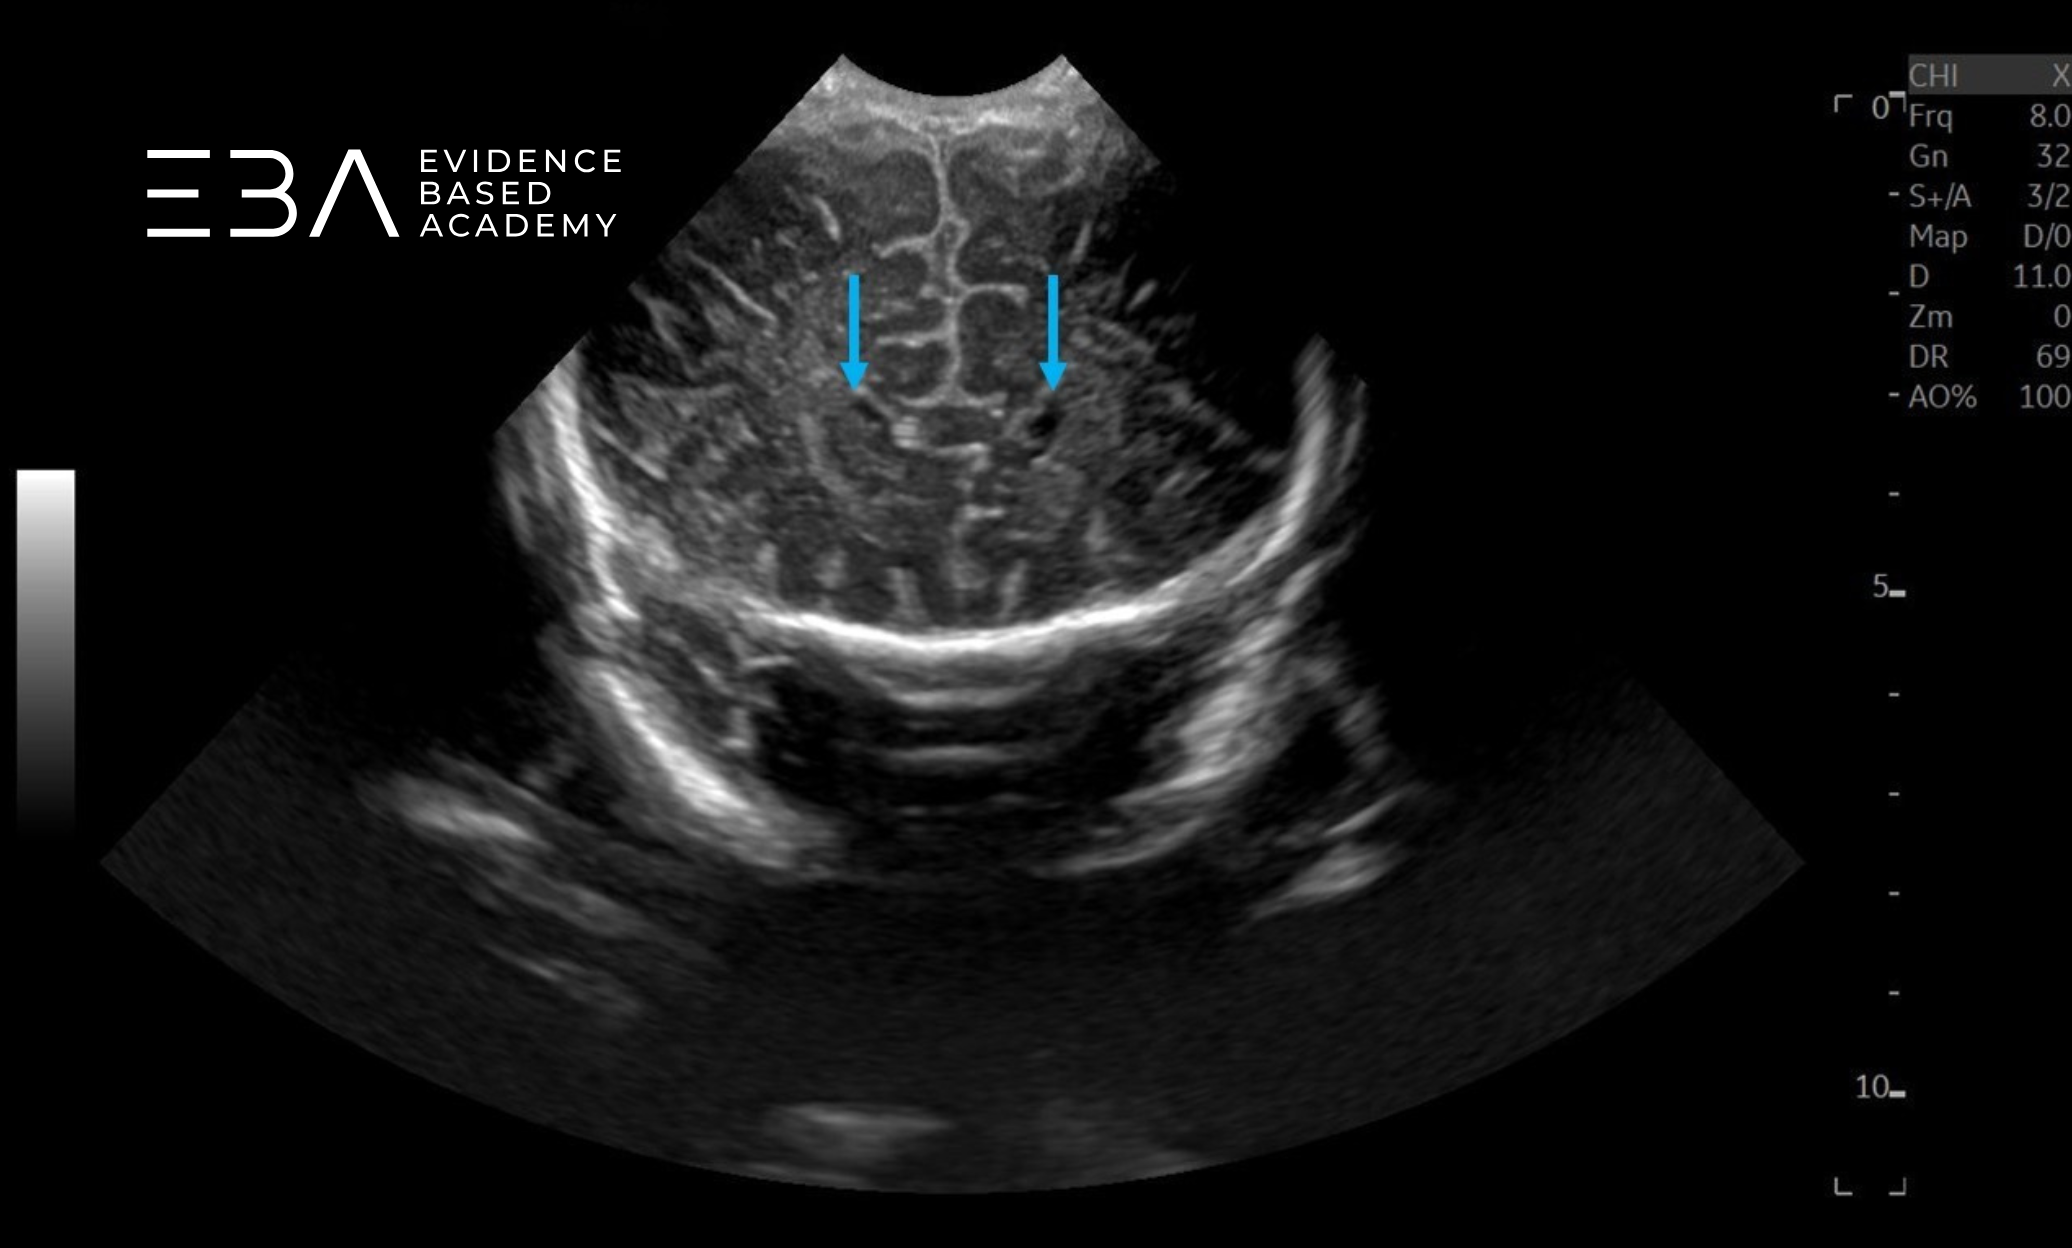

Projekcja 4 – na poziomie trójkątów: widoczne są komory boczne na poziomie splotów naczyniówkowych i istota biała okołokomorowa. Wzgórza ograniczają komory boczne od dołu. Splot naczyniówkowy jest widoczny jako echogeniczne struktury – na stropie komory trzeciej i wzdłuż dna komór bocznych. Powyżej hipoechogenicznych półkul móżdżku widoczny jest hiperechogeniczny namiot móżdżku, a poniżej wzgórz – hipoechogeniczne konary mózgu (3, 6).

zdj. 14

Głowica liniowa. Strzałkami zaznaczono tylne części splotów naczyniówkowych.